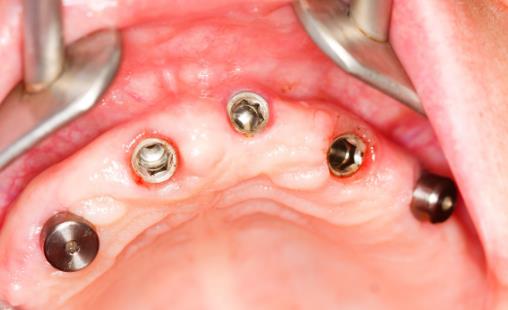

種植牙有哪些過程

牙齒種植一般需要經歷三個階段:

1、手術前準備:術前主要的工作是拔掉壞牙的殘根,治療存在的牙周疾病等等,為后期種植做好準備,這個過程的時間長度完全依據情況而定,有的人需要幾個月,有的人一兩天就處理完成了。

2、植入階段:根據醫生的設計方案,通過手術把植體植入到牙槽骨內部,手術需要局部麻痹,大概時長10-20分鐘。

3、義齒修復階段:手術后3-6個月,開始安裝牙冠或者義齒。主要包括取模、義齒制作,戴牙等過程,這個過程大概經歷2-3周。